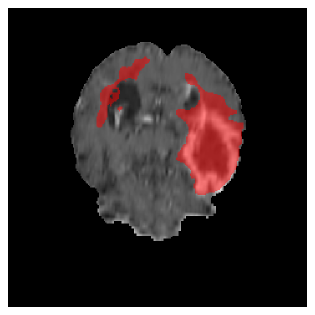

Appendix A Qualitative results

Figures 4 and 5 present the segmentation results for a patient from the BRATS dataset, visualized on a randomly selected slice. Figure 4 illustrates how tumor segmentation evolves over multiple episodes in S1 across different approaches including cumulative, naive, our approach, and the best buffer-free strategy (SI, =2). The cumulative approach, which trains on all encountered datasets together, maintains segmentation consistency across episodes but introduces significant amounts of false positives, particularly in the upper left area of the brain images. These misclassifications highlight its inability to generalize well across datasets despite access to all previous data. The naive approach, which learns sequentially without any continual learning strategy, suffers from severe catastrophic forgetting. While it initially segments well, performance deteriorates over episodes, leading to a near-complete loss of segmentation capability by the final episode. The SI (=2) approach, a regularization-based buffer-free CL strategy, performs reasonably well in early episodes but shows a significant performance decline over time. By the last episode, much of the tumor was no longer segmented, indicating difficulty in retaining prior knowledge. In contrast, our proposed approach initially produces more false positives but progressively refines its segmentation. By the final episode, it accurately retains the tumor region while minimizing misclassifications, demonstrating strong knowledge retention and adaptability across episodes. This suggests that our approach effectively mitigates catastrophic forgetting while maintaining segmentation performance over sequential learning.